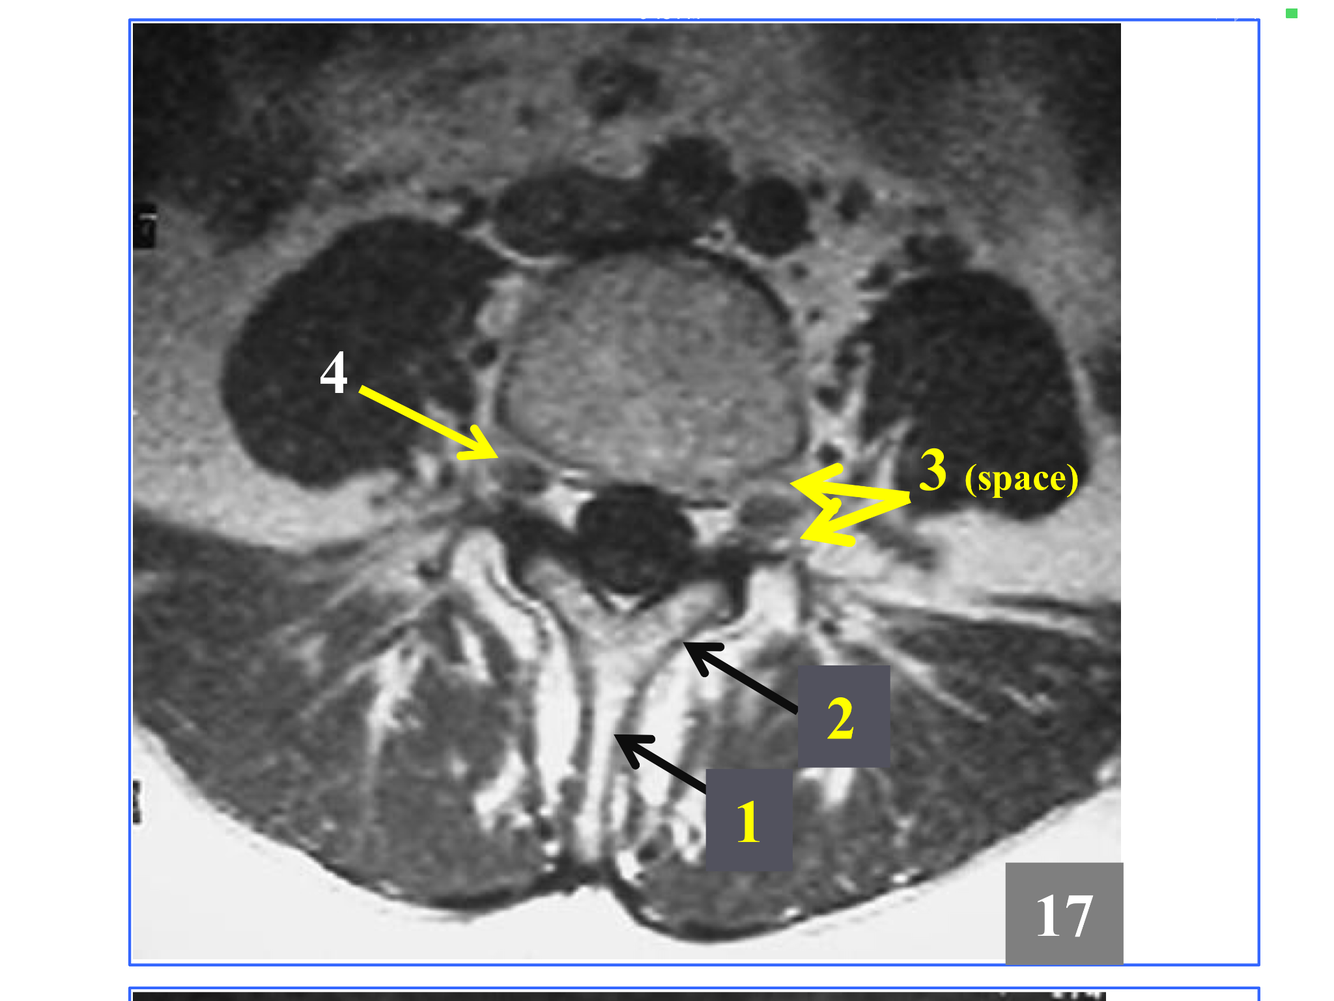

* The stack of inferior and superior articulating processes, and the zygapophyseal joints they form

*Comprised of the inferior and superior articulating processes, and the zygapophyseal joints they form

*Immediately above the conus, which is at L1-L2

* Not seen in its entirety